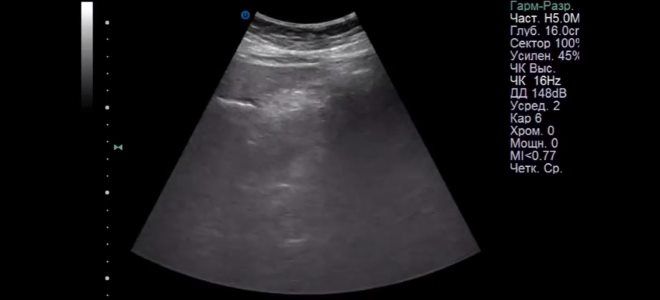

- УЗИ.